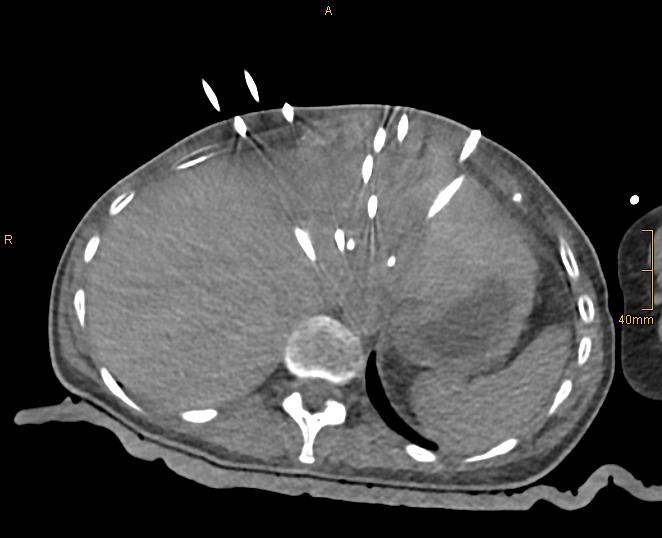

Figure 1B: Control CT with 15 coaxial needles in place.

In the meantime, we have treated > 900 patients with > 3000 liver tumors in > 1500 sessions and collected them in our prospective SRFA registry. After bridging therapy with SRFA for liver transplantation, complete histopathological response was found in 183 of 188 treated lesions (97.3%) and in 50 of 52 lesions > 3cm (96.2%) 2. In a recent paper reporting the results after SRFA of very large tumors (> 8 cm) 3 (Figure 1) and in other studies including primary and secondary liver tumors the short- and long-term outcomes after SRFA were comparable to HR.